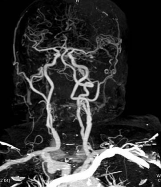

Рис. 3. - КТ ангиография сосудов головы и шеи с

использованием

двухэнергетической КТ на аппарат с двумя

источниками излучения.

Реформация во фронтальной проекции, MIP. Костные

структуры

черепа и верхней апертуры математически выделены

и удалены

Одним из возможных направлений развития этой

методики является быстрое, еще в процессе построения изображения, разделение

костных структур, мягких тканей и паренхиматозных органов, а также

контрастированных йодсодержащими веществами сосудов. Это позволят построить изображения,

как двухмерные, так и трехмерные, с исключением одной или двух из перечисленных

трех групп анатомических структур. В ряде случаев искусственное удаление

костных структур может иметь большое диагностическое значение. Например, при

исследовании головного мозга или области верхней апертуры грудной клетки

исключение из построенного изображения костных структур позволяет более точно

понять расположение сосудов и окружающих мягких тканей. Сегодня эту процедуру

можно выполнить с помощью специально программного обеспечения, однако она много

занимает времени и требует участия специалиста.